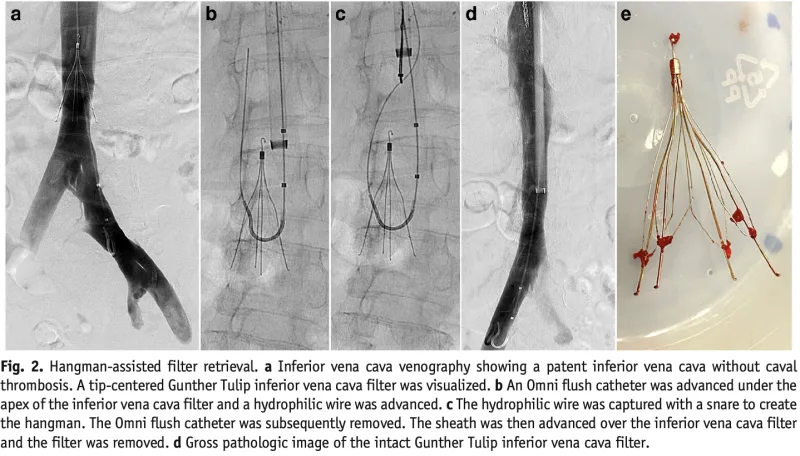

フィルターは, 傘の骨のような構造で, 血管の中で拡がり, 血栓が肺に流れていくのを防ぎます.

しかし, 総腸骨静脈には血栓が残存していたため, 明後日, 心臓血管外科で下大静脈フィルターを留置してもらう方針となりました.